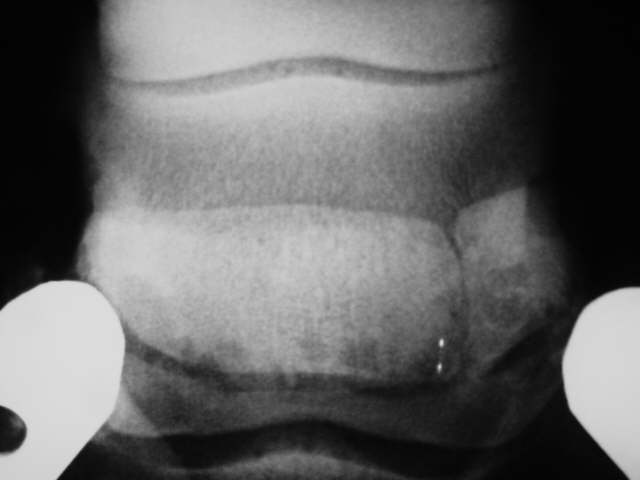

Strahlbeinfraktur Röntgenklasse IV